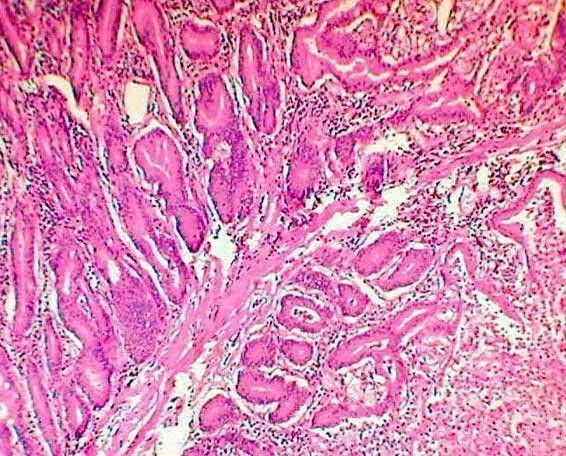

tejido.jpg

TEJIDO MUSCULAR.cmap